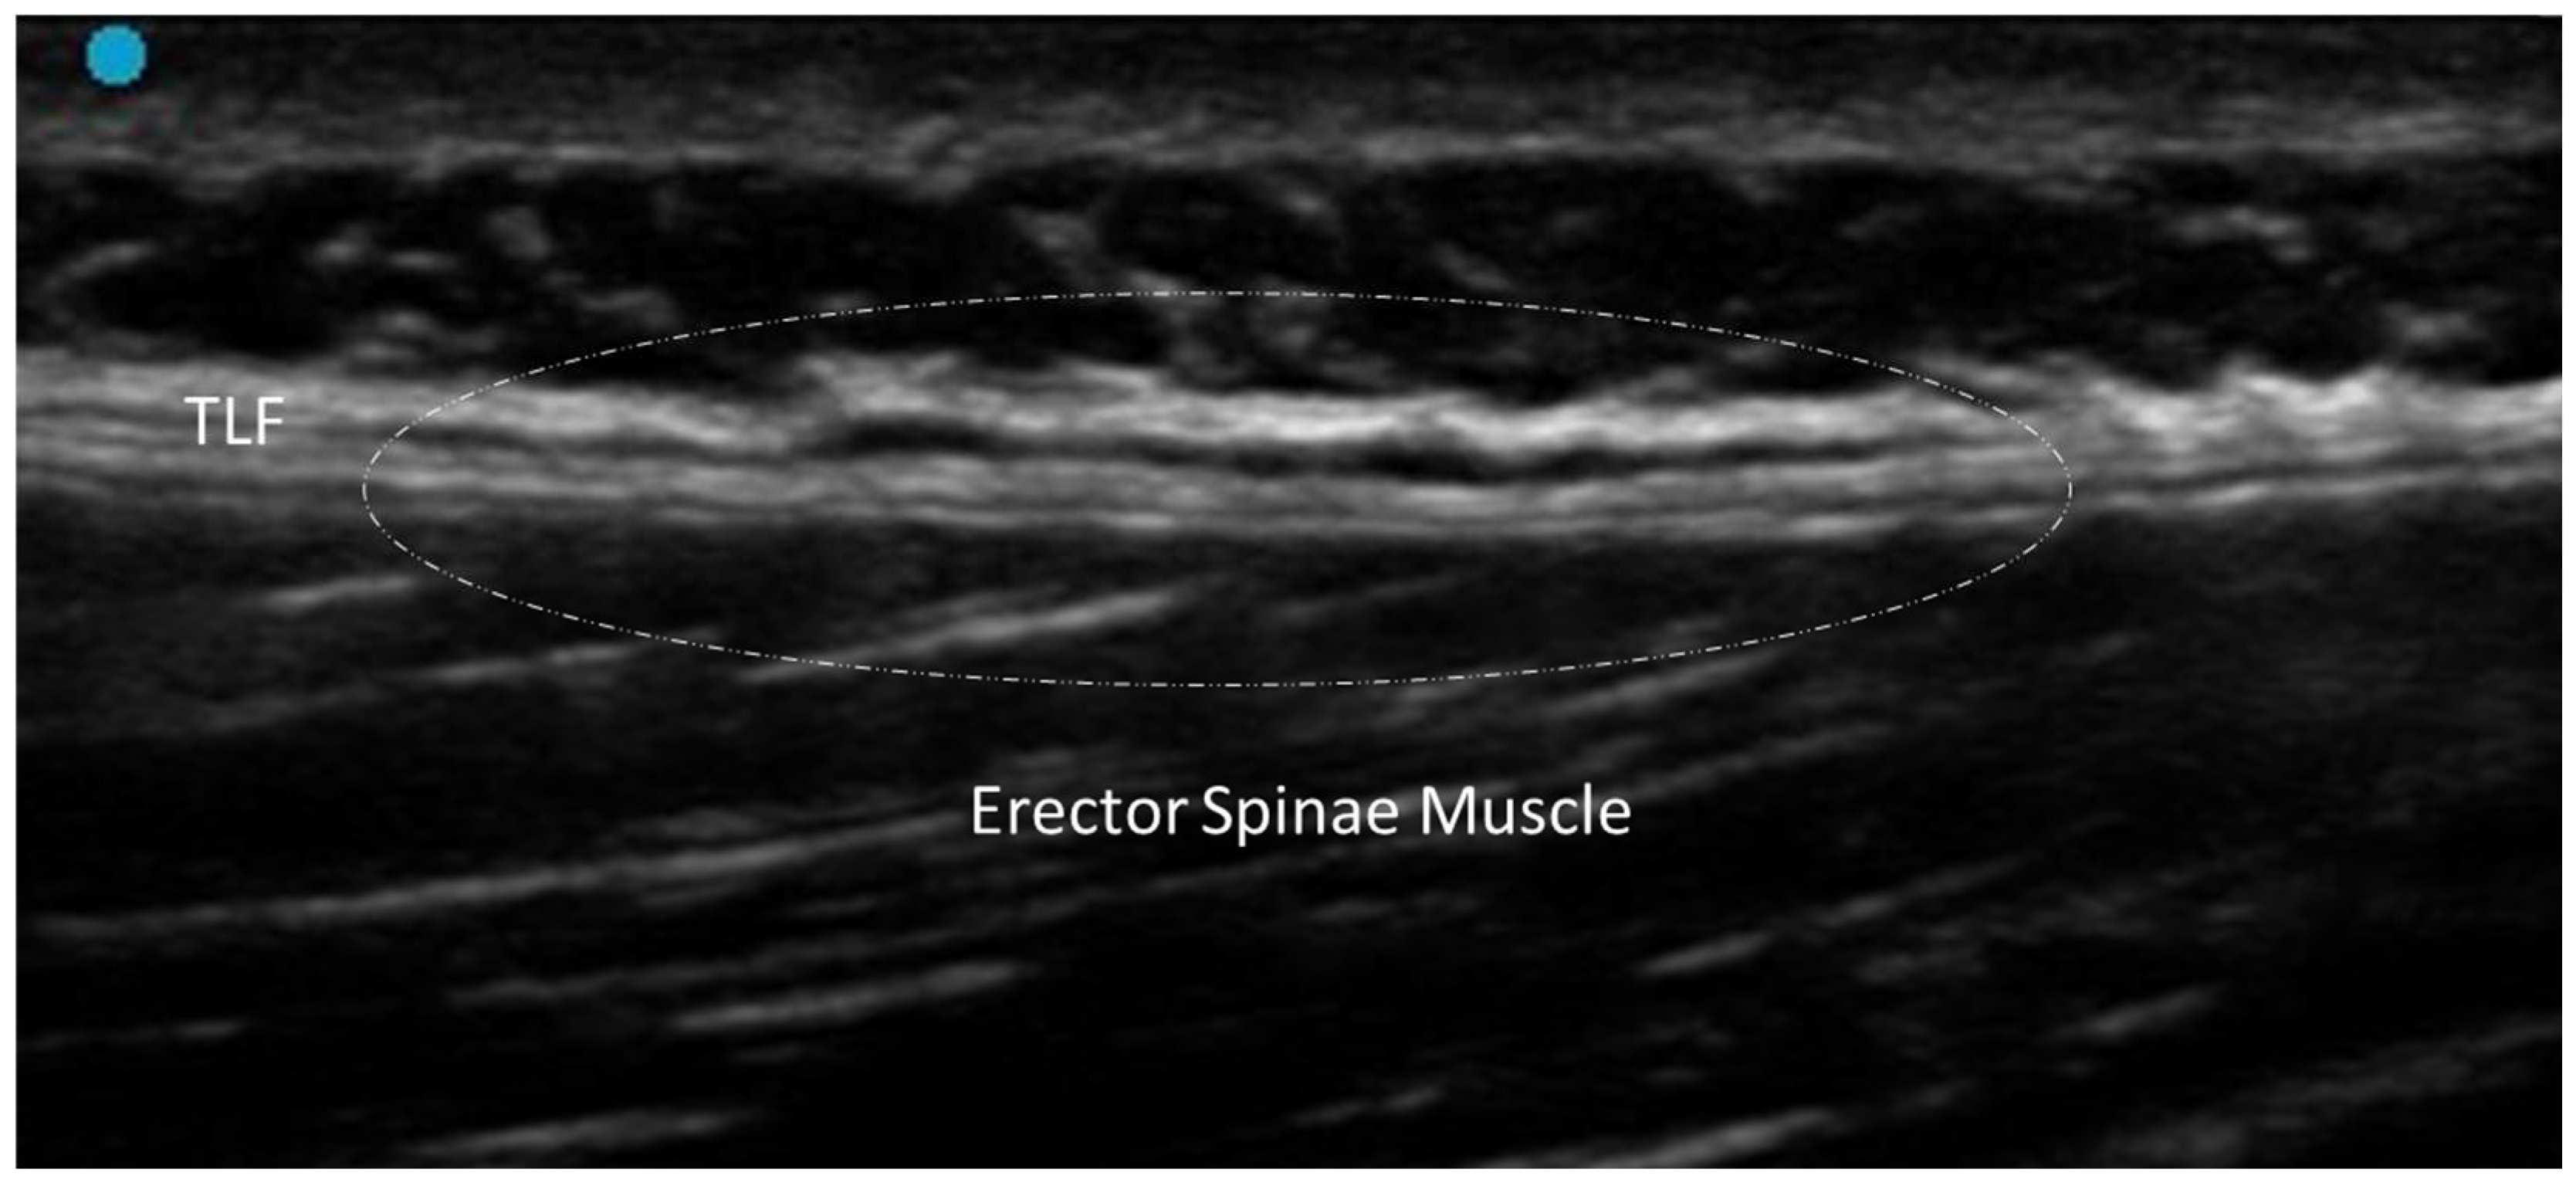

- Pirri, C.; Pirri, N.; Guidolin, D.; Macchi, V.; Porzionato, A.; De Caro, R.; Stecco, C. Ultrasound Imaging of Thoracolumbar Fascia Thickness: Chronic Non-Specific Lower Back Pain versus Healthy Subjects; A Sign of a “Frozen Back”? Diagnostics 2023, 13, 1436. [Google Scholar] [CrossRef] [PubMed] [PubMed Central]

3.2.2. Densification